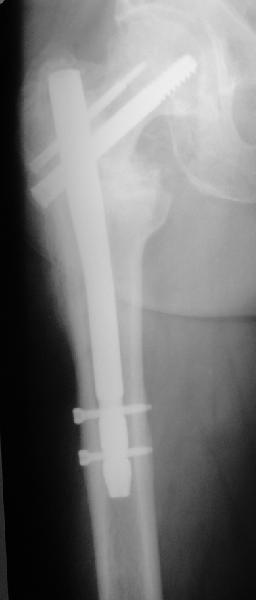

[Ortho] Ложный сустав базальной части шейки бедра

Закрытый интрамедуллярный остеосинтез или он же в сочетании с чрескожной межвертельной остеотомией в случае внесуставного несращения - это, по сути, эндопротезирование с собственной шейкой и головкой бедра. Но через 3-4 разреза по 1,5-2 см. Нога сразу опорная, сустав конгруэнтный - чего еще надо? В приложении - похожее несращение тоже у пациента за 60 и с диабетом 2 типа...